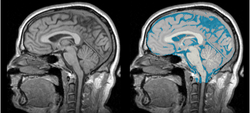

Physiological Brain Activity Longitudinal Study

- Collaborator: Laura Horky PI (Brigham and Women's Hospital(BWH)), Jon Hainer (BWH), Wendy Plesniak (BWH), Alexander Zaitsev (BWH), Ron Kikinis (BWH) and BWH Division of Nuclear Medicine

- Short description: Evaluate glycolitical brain activity in CSF and White Matter for the patients undergoing chemical therapy courses.

- Image specification: 1.5 Tesla ,Scanner: SIGNA EXCITE / GE MEDICAL SYSTEMS, T1, Axial Scans, TR/TI/TE=500/0/21 ms, pixel_xsize = 0.781251, pixel_ysize = 0.781244, fov = 0.000000, aspect = 7.679990, thick = 5.000000, space = 1.000000

- Used Task: MRI Human Brain Hemisphere